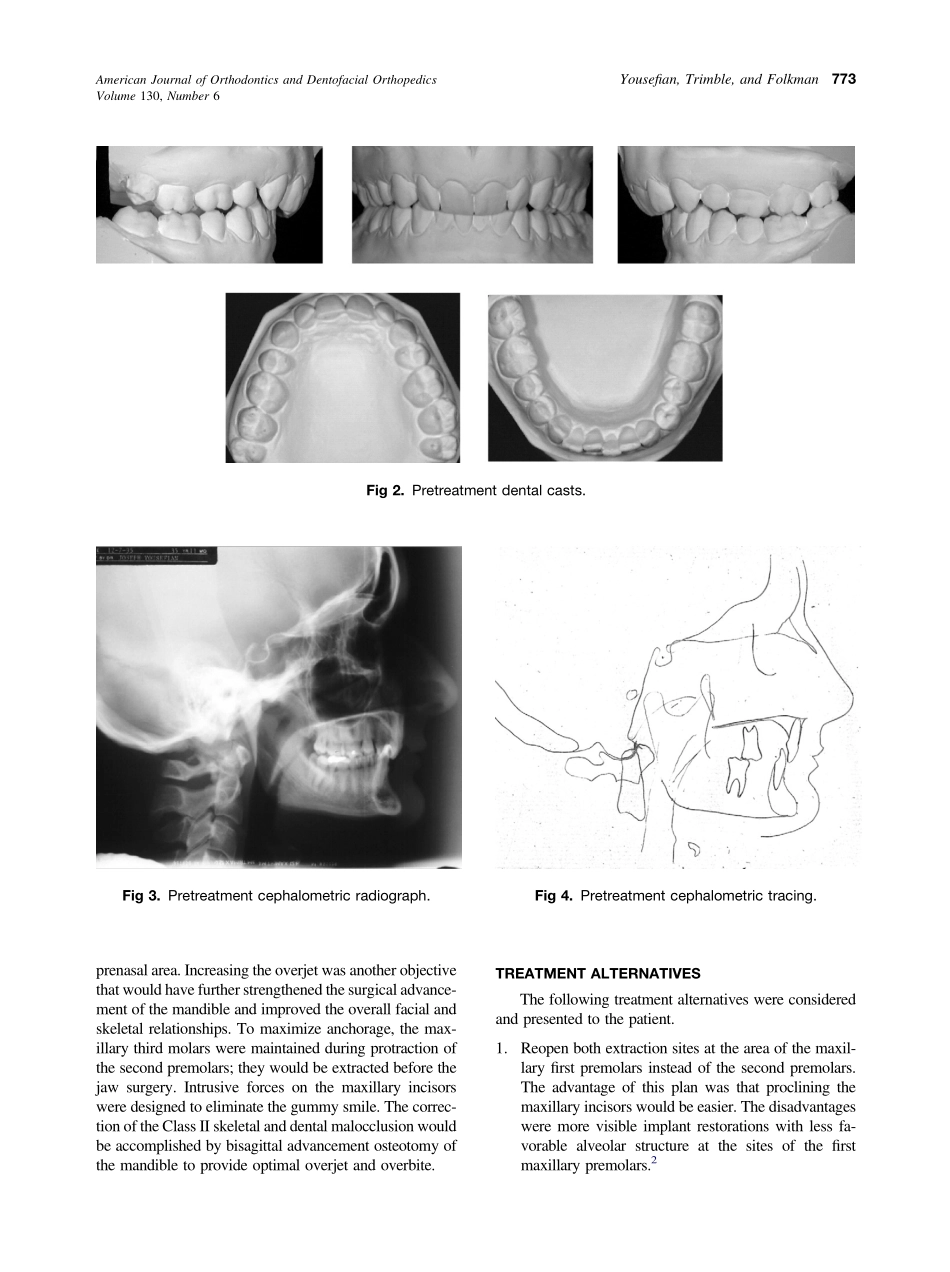

CASEREPORTAnewlookatthetreatmentofClassIIDivision2malocclusionsJosephYousefian,aDouglasTrimble,bandGaryFolkmancBellevueandIssaquah,WashThiscasereportillustratesatreatmentoptionformanagingaskeletalC...